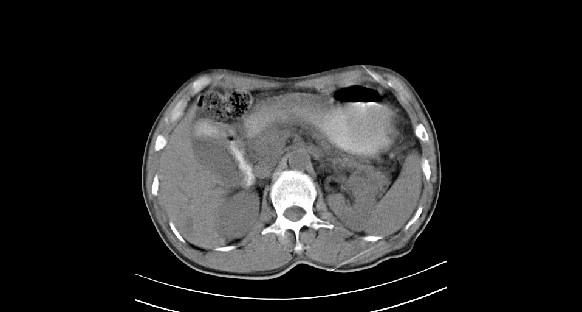

男性,70岁,体检b超发现左肾占位,请各位战友发表一下观点

左肾有两个病灶,且较大的病灶内可见点状钙化灶,增强扫描边缘也是呈渐进性强化,中央部分未见明显强化